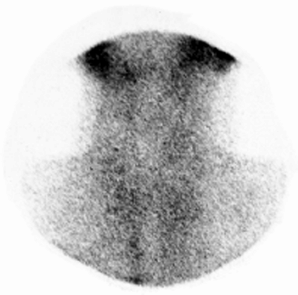

En 22 casos de TSA vistos durante las primeras 6 semanas, se realizó cintilograma tiroideo. En 72,73 %, la supresión de la captación tiroidea de yodo radioactivo no permitió la visualización de la tiroides en el examen, al presentar valores de captación entre 0 % y 9 %, con X±1DS 2,41±2,88 % (Figura 4 y Figura 5). En 5 casos (22,73 %), con captación tiroidea entre 10 % y 28 %, el cintilograma reveló áreas focales o nódulos hipocaptantes, aumento del volumen glandular y captación heterogénea del trazador. Un último caso con captación tiroidea de 8 % sólo mostró distribución heterogénea del trazador.

Figura 4. Cintilograma tiroideo en la fase de comienzo de la tiroiditis subaguda con tirotoxicosis.

La baja concentración del trazador en el parénquima tiroideo (captación I-131/24h 5 %, VN 15 %-45 %) no permitió la visualización de la tiroides. Se observa acumulación del material radioactivo en las glándulas salivales y en la cara anterior del cuello se aprecia abundante cantidad del trazador en forma libre circulante.